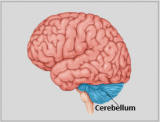

A neuroanatomia é o ramo da anatomia que estuda a anatomia do sistema nervoso, ou seja, a estrutura, a função e a organização do sistema nervoso. O sistema nervoso é um dos sistemas mais complexos do corpo humano e inclui o cérebro, a espinal medula, os nervos periféricos e os gânglios nervosos. A neuroanatomia preocupa-se com a forma como estas estruturas estão ligadas entre si, como os sinais são transmitidos entre as células nervosas e como as diferentes partes do sistema nervoso trabalham em conjunto para controlar as funções corporais e cognitivas. Os neuroanatomistas utilizam técnicas de imagiologia avançadas, como a ressonância magnética (MRI), a tomografia por emissão de positrões (PET) e a microscopia para visualizar as estruturas e funções do sistema nervoso.